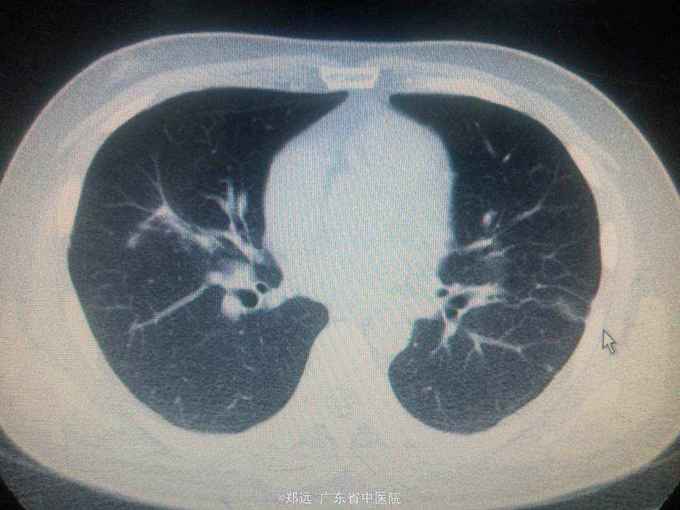

体查:双下肺湿啰音。三尖瓣区3/6级收缩期杂音。 胸部ct:双肺斑片结节影并空洞形成,左胸少量积液。血色素88克/升,白细胞11.48,中性粒81.3%,降钙素原14.84,ALT 121,AST 134.超声提示三尖瓣赘生物,三尖瓣大量返流。血培养金葡菌。

诊断:急性感染性心内膜炎,脓毒症,肺脓肿,丙型肝炎。 治疗:入院予万古霉素0.5克q6h,经治疗五日血象正常,降钙素原1.54,但仍反复高热,考虑肺脓肿合并阴性菌感染,加用头孢哌酮舒巴坦3克q12h,治疗五日仍有发热,血培养阴性,白细胞正常,降钙素原0.15,头孢哌酮舒巴坦改为美罗培南0.5克q8h,两日后无再发热,维持该方案至治疗四周后改予万古霉素0.5克q8h加美罗培南0.5克q12h继续治疗两周,复查超声提示三尖瓣熬生物较入院时缩小约三分之一,多次血培养阴性,胸部ct提示肺部炎症明显吸收予出院。出院后患者仍间发热,出院后约七周再次返院,查白细胞13.88,中性粒65.9%,血色素正常,降钙素原0.55,血培养提示溶血葡萄球菌,胸部ct示双肺多发感染灶,较前吸收,胸腔积液已吸收。予原万古霉素加美罗培南方案治疗,两日后无发热,治疗三周后多次血培养阴性,胸部ct提示肺部感染基本吸收,行三尖瓣赘生物切除并三尖瓣修补术,术中见三尖瓣后瓣瓣叶破坏严重,赘生物大小约2*1厘米。术后恢复良好,维持万古霉素加美罗培南治疗一周后改予万古霉素0.5克q8h加阿米卡星0.4克q12h治疗两周,赘生物及多次血培养阴性予出院。